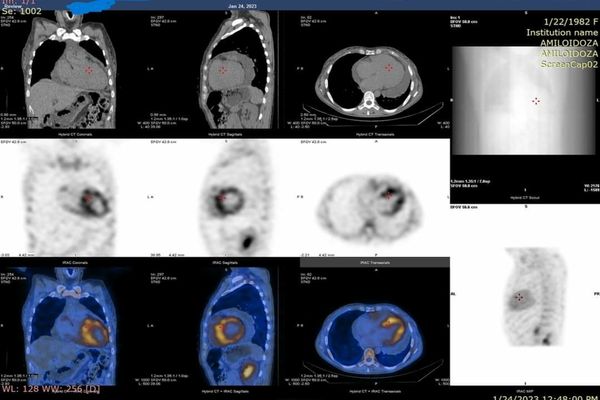

28 mar. 2023, 12:35SocialO nouă investigație modernă accesibilă în SJU. Scintigrafia cu difosfonați, metodă pentru diagnosticul amiloidozei ereditare